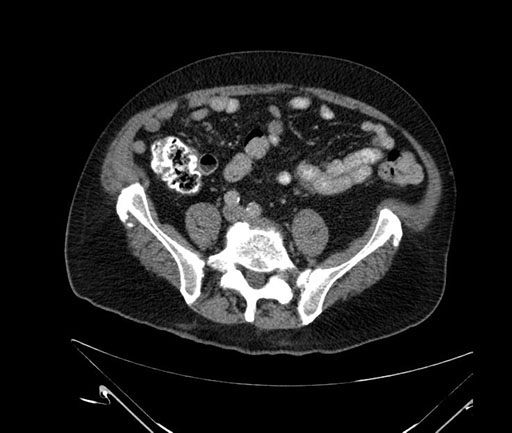

Whipple (pancreaticoduodenectomy) [case 7]

Axial - 3 months prior